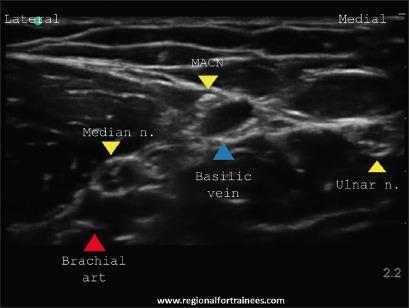

Upper extremity surgery is commonly performed under regional anesthesia. The advent of ultrasonography has made performing upper extremity nerve blocks relatively easy with a high degree of reliability. The proximal approaches to brachial plexus block such as supraclavicular plexus block, infraclavicular plexus block, or the axillary block are favored for the most surgical procedures of distal upper extremity. Ultrasound guidance has however made distal nerve blocks of the upper limb a technically feasible, safe and efficacious option. In recent years, there has thus been a resurgence of distal peripheral nerve blocks to facilitate hand and wrist surgery. In this article, we review the technical aspects of performing the distal blocks of the upper extremity and highlight some of the clinical aspects of their usage.

上肢手术通常在区域麻醉下进行。超声检查的出现使得进行上肢神经阻滞相对容易,且可靠性高。对于大多数上肢远端的外科手术,臂丛神经阻滞的近端入路,如锁骨上神经丛阻滞、锁骨下神经丛阻滞或腋路阻滞,是比较常用的。然而,超声引导使得上肢远端神经阻滞成为一种技术上可行、安全且有效的选择。近年来,远端周围神经阻滞因此再度兴起,以方便手部和腕部手术。在本文中,我们回顾了进行上肢远端阻滞的技术要点,并强调了其使用的一些临床方面。